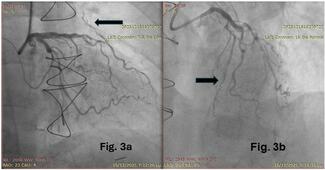

06:01: The next article was one about iodixanol to see if it could reduce adverse renal or cardiac events in CTO interventions from the CARE-CTO study, which is a sub-study of the PROGRESS-CTO registry from Dr Brilakis from Minneapolis Heart Institute and colleagues. What they found in an observational study was that iodixanol did appear to reduce complications. Obviously, randomized clinical trial data would be preferable in this sort of situation, but short of that, encouraging data with respect to that particular contrast agent.